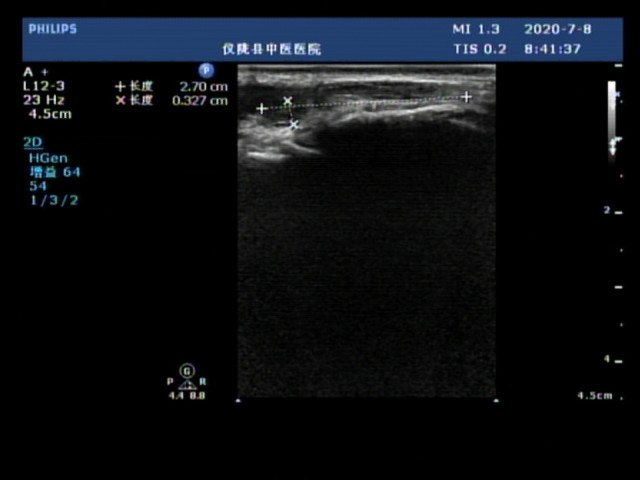

动静脉内径:测量时应尽量与血管走行保持平行或垂直,避免夸大或缩小管腔内径。测量浅表静脉(如贵要静脉、头静脉)时,患者应配合保持静息状态,避免影响其内径评估。

测量位置一般在内瘘静脉侧,测量时应尽量将血管内径显示到最大,取样容积应包含全部管腔宽度。取得频谱后,可手动或设备自动测量出血流平均速度计算得到血流量。若超声发现血流量不足,应注意询问患者瘘口处震颤是否减弱或消失,以验证超声测量结果是否准确合理。内瘘静脉距体表深度 < 6 mm。连续至少 8 cm 长的内瘘静脉内径均 ≥ 5 mm,且均距离体表 < 6 mm。